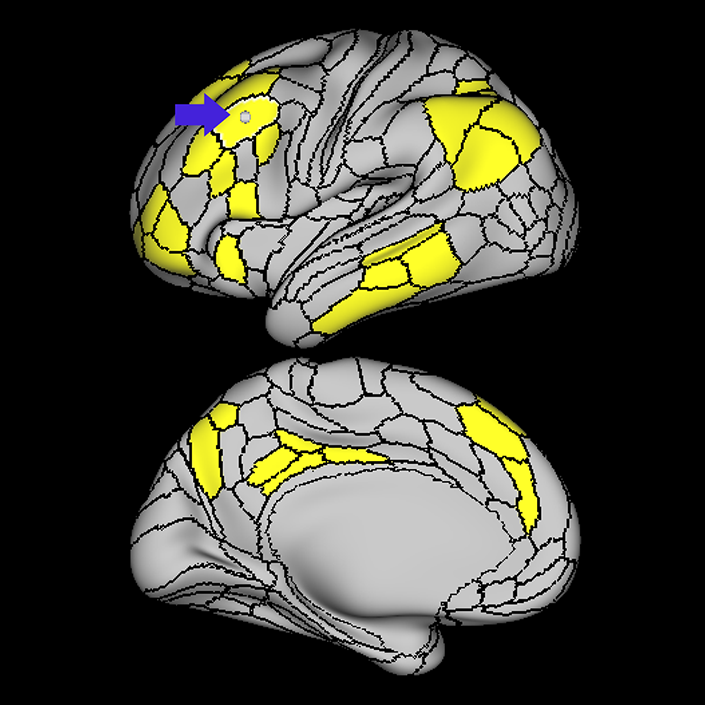

ᐅ SummaryArea STSdp (superior temporal sulcus dorsal posterior): part of the temporal lobe regions. Involved in motion processing, audiovisual integration, and facial processing. The posterior half of STSdp (as with STSvp) is strongly activated in the story-math secondary contrast, indicating a role in language comprehension. STSdp responds more strongly than STSvp to primary language tasks and to social cognition and motor tasks. ᐅ Where is it?Area STSdp (superior temporal sulcus dorsal posterior) is found on the posterior half of the lateral face of the STG and the posterior half of the superior bank of the superior temporal sulcus ᐅ What are its borders?Area STSdp borders area STSda anteriorly, STSvp inferiorly, TPOJ1 posteriorly, and A5 superiorly. ᐅ What are its functional connections?Area STSdp demonstrates functional connectivity to areas 9m, 8BL, 44 45, 47L, 47s, IFSp, SFL and 55b in the frontal lobe, areas STV, PSL, A5, and STGa in the insula opercular area, areas STSva, STSvp, STSda, and TGd, in the temporal lobe, TPOJ1 in the lateral occipital lobe, and PGi and 31pd in the parietal lobe ᐅ What are its white matter connections?Area STSdp is structurally connected to the "u" fibers of the occipito-temporal system and the arcuate/SLF. Arcuate/SLF tracts wrap around the Sylvian fissure projecting toward the frontal lobe and turn medially to terminate at 44, FOP4, IFJa, IFJp and IFSp. Local short association fibers include "u" fibers of the occipito-temrporal system that connect to STSda, STSva, STSvp, PSL and P ᐅ What is known about its function?The posterior portion of the STS is primarily involved in motion processing, audiovisual integration, and facial processing. The posterior half of STSdp (like the posterior half of STSvp) is strongly activated in the story-math secondary contrast, indicating a role in language comprehension. STSdp responds more strongly than STSvp to primary language tasks and to social cognition and motor tasks. |

A: lateral-medial

B: anterior-posterior

C: superior-inferior

DTI image |